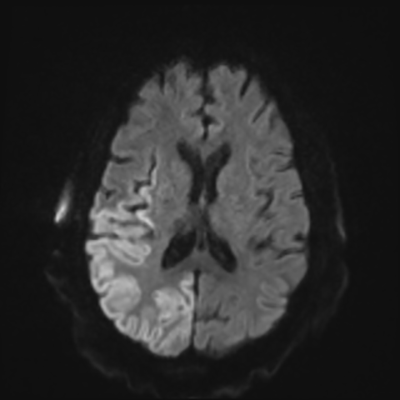

You come back the next day and see how things are going. The patient's electrographic record has shown a moderate encephalopathy (diffuse slowing, disorganization) with frequent right posterior quadrant delta slowing. Based on this result, and an adequately improved clinical examination, you give the okay to proceed with obtaining an MRI of his brain. This is shown below.

MRI brain (DWI)